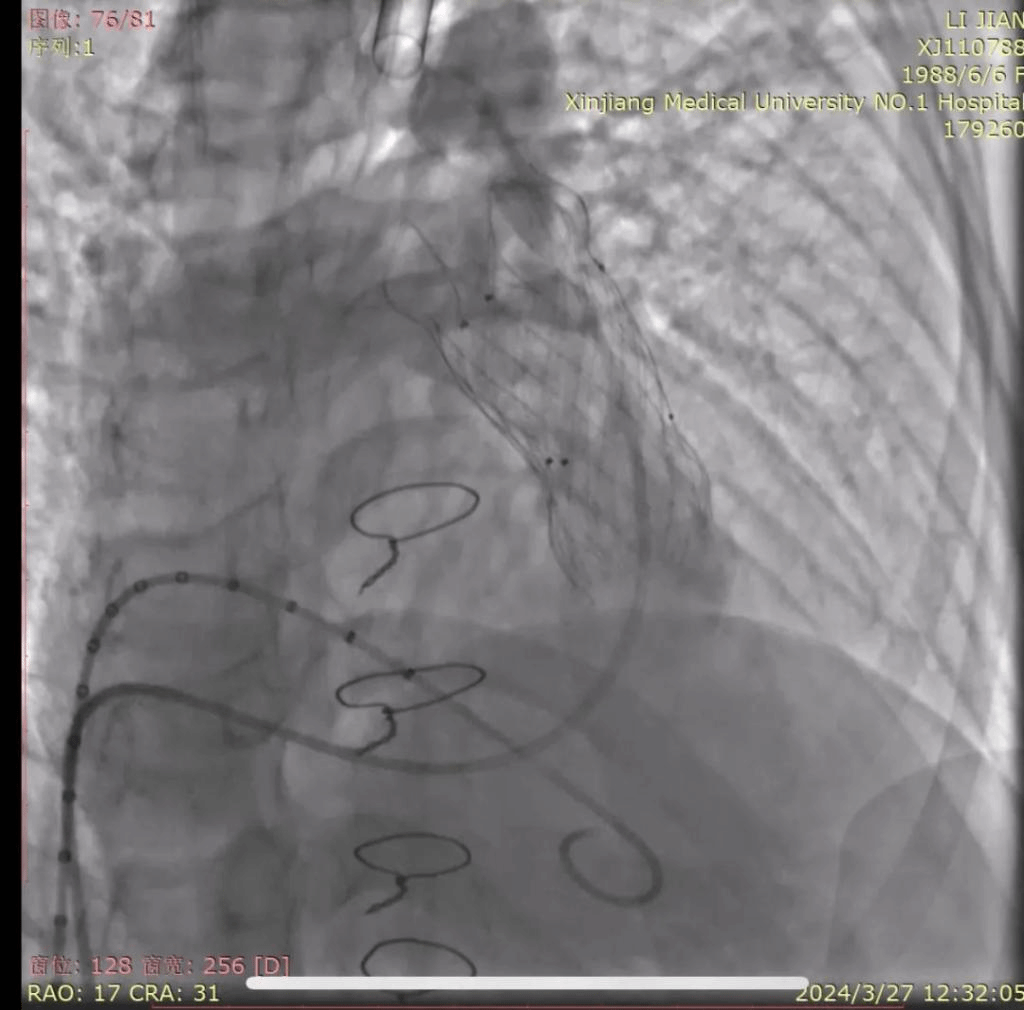

术中,马翔主任医师、刘成副主任医师联合四川大学华西医院冯沅教授实施手术,术中造影可见大量肺动脉瓣反流,沿右股静脉—下腔静脉—右心房—右心室—肺动脉送入超硬导丝建立轨道。根据测径球囊的测量,选用P30-25型号的VenusP-Valve瓣膜,至肺动脉分叉处开始释放,释放完成后重复造影可见人工瓣膜位置准确,形态良好,未见明显肺动脉瓣反流及瓣周漏。术后即刻拔除气管插管,手术成功。

图中显示VenusP-Valve瓣膜释放完成,造影显示位置准确,形态良好,无明显瓣膜反流及瓣周漏;